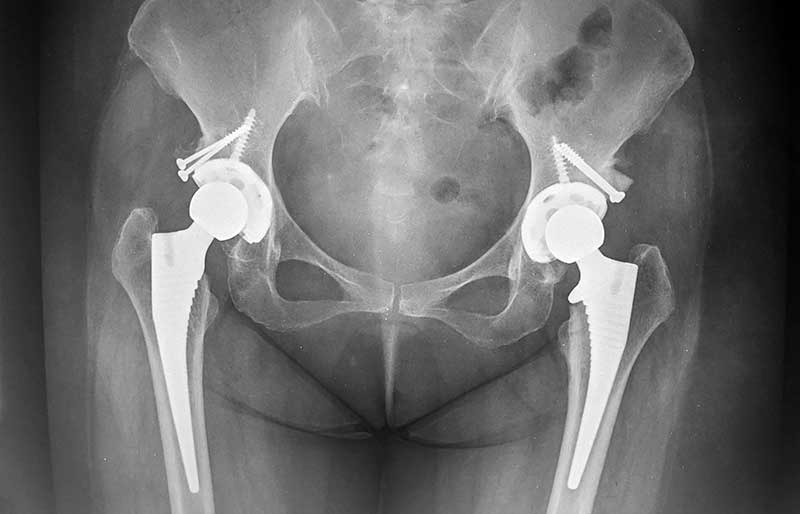

Operasi penggantian sendi panggul adalah suatu operasi untuk mengganti sendi panggul yang rusak dengan sendi buatan yang disebut prosthesis. Penyebab utama kerusakan sendi panggul adalah osteoartritis (baca penjelasan tentang “Osteoartritis”) dan sendi panggul adalah sendi terbanyak kedua setelah lutut yang terserang penyakit ini.

Operasi penggantian sendi panggul merupakan pengobatan terbaik untuk osteoartritis panggul stadium yang berat. Ada empat tujuan operasi ini, yaitu menghilangkan rasa sakit sendi yang telah rusak, memperbaiki lingkup gerak sendi yang sebelumnya kaku dan terbatas, mengembalikan kemampuan penderita melakukan aktivitas harian tanpa rasa sakit, dan meningkatkan kualitas hidup sehingga penderita kerusakan sendi dapat menjalani hidup secara aktif bebas dari nyeri sendi panggul.

Operasi penggantian sendi panggul biasanya berlangsung sekitar 1,5 sampai 2 jam. Sama seperti operasi yang lain, di jaman modern ini operasi penggantian sendi panggul merupakan operasi yang aman bagi orang tua (pada kenyataannya, sebagian besar penderita osteoartritis sendi panggul adalah para orang tua). Dengan kemajuan teknologi dan ilmu kedokteran modern, operasi penggantian sendi panggul aman bagi orang tua yang biasanya juga menderita kencing manis, penyakit jantung dan tekanan darah tinggi.